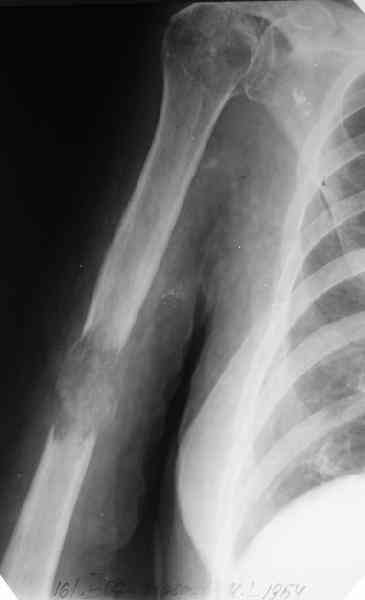

Патологические переломы плеча

Женщина 53 лет получила патологический перелом правого плеча в феварле, и левого в марте - mts из невыясненного первичного очага.

Онкологи провели облучение, руки на косынки, время от времени наблюдают, вводили зомету.На нас вышли родственники. Состояние пациентки уже не очень, анемия (Hb -50-60 г/л), исхудалв, но асцита нет, в легких чисто. Поскольку женщина совершенно беспомощна, решили сделать остеосиннтез.

Сегодня сделали, Fixion диаметром 7,4 мм. Обе пперации продолжались по 7 мин. Картинки в приложении. Наркоз был диприваном, на спонтанном дыхании. По крайней мере, пока довольны хотя бы анестезиологи, похоже, не верили, что управимся меньше, чем за час ;-)

Гвоздик 7,4 расширяется до 11 мм. Не маловато ли, судя по снимкам?